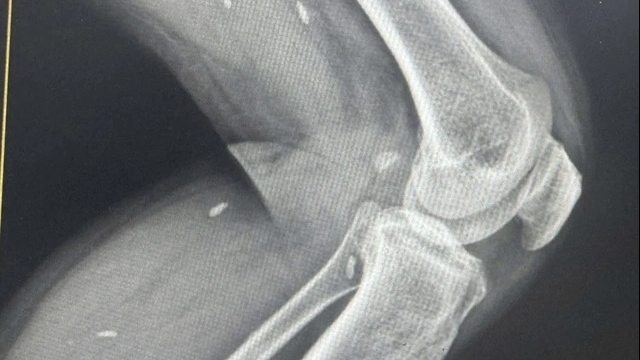

![]() |

| Phần tay của ông P đã bị hoại tử (Ảnh; BVCC) |